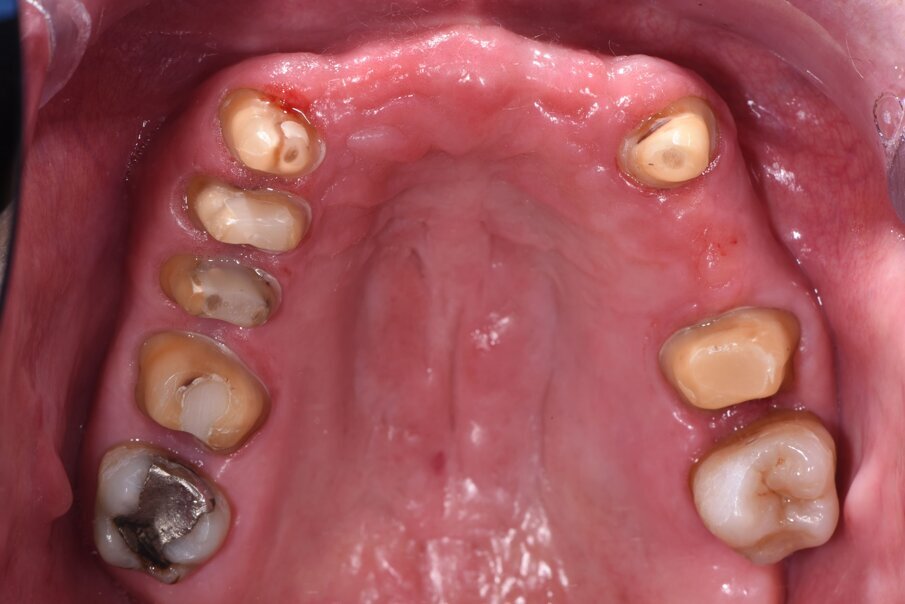

Il caso clinico descrive una situazione complessa di una paziente trattata con radioterapia 5 anni prima per un carcinoma della laringe, in conseguenza del quale era stato rimosso l’intero gruppo incisivo superiore sostituendolo provvisoriamente con una protesi parziale rimovibile stabilizzata con ganci a filo sui canini (Fig. 1). La paziente di 59 aa presentava inoltre delle protesizzazioni fisse nel quadrante I° e III° su elementi naturali, entrambe con vistose infiltrazioni e scheggiature che rendevano i manufatti incongrui. Lo stato parodontale iniziale presentava un sondaggio medio (Tab. 1) spesso associato a mobilità di vario grado e per taluni elementi era presente anche sanguinamento. All’esame obiettivo si evidenzia una complessa situazione clinica riportata di seguito in Tabella 2.

Fig. 1_Foto iniziale con il provvisorio rimovibile in posizione. La presenza di una flangia in resina consente un maggior supporto labiale.

Fig. 17_Visione occlusale a preparazione degli elementi naturali ultimata in preparazione orizzontale a chamfer.